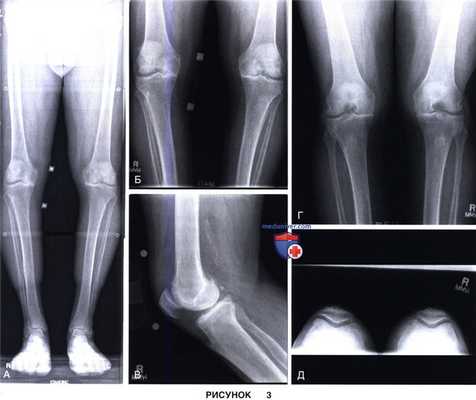

а) Предоперационное рентгенологическое обследование пациента включает рентгенографию конечности целиком на длинной кассете, рентгенографию стоя в переднезадней проекции, стоя в задне-передней проекции при сгибании коленного сустава, в боковой проекции и проекции Merchant (рис. 3).